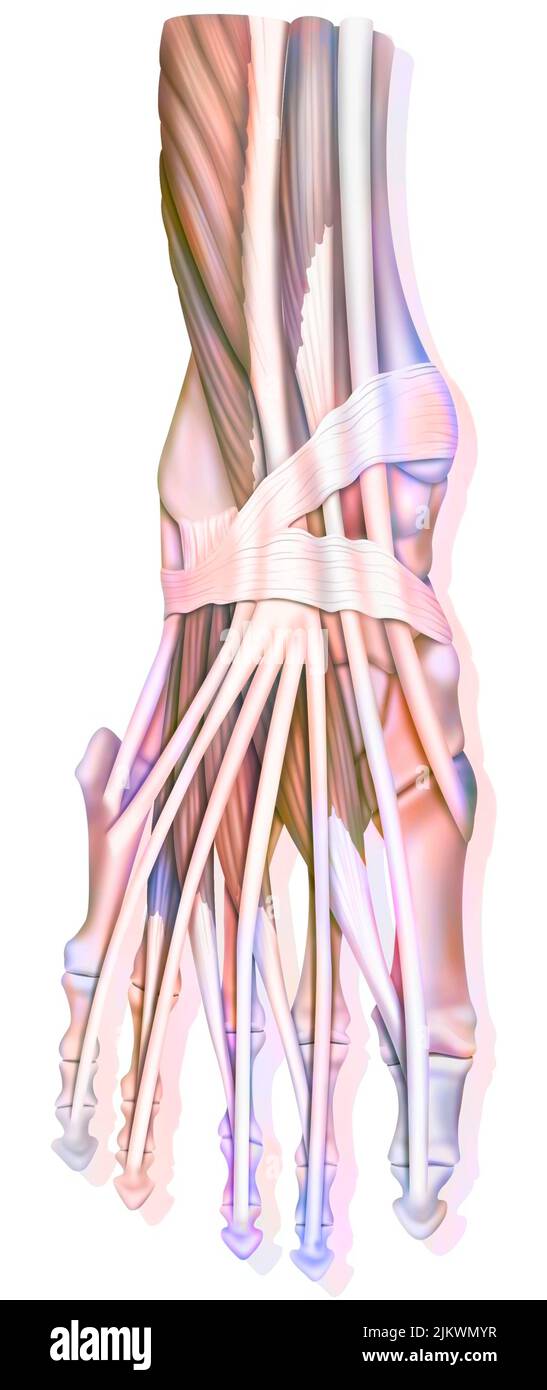

RF2ABM669–La médecine et les soins de l'illustre le tableau, les droits de l'anatomie du pied : Peau et tissus ectodermaux, os, muscles nerfs, vaisseaux sanguins